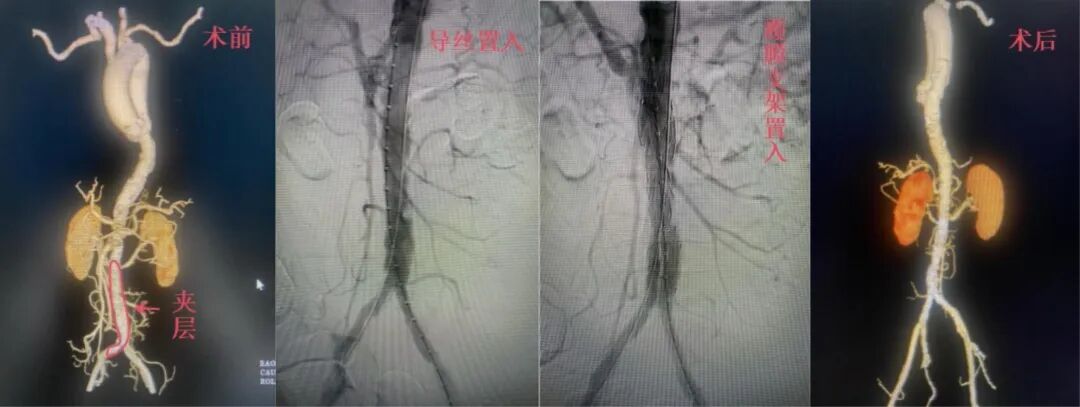

高龄、复杂基础病患者同样获得有效救治。今年1月,一名74岁女性因反复腹痛就诊,检查提示主动脉多发溃疡、腹主动脉夹层,合并多支内脏血管重度狭窄,血管条件极差。团队制定个体化方案,成功完成腹主动脉覆膜支架腔内隔绝术,解除致命威胁。